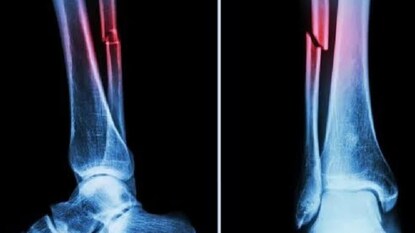

മെഡിക്കല് രംഗത്ത് വിപ്ലവം സൃഷ്ടിക്കുന്ന കണ്ടുപിടിത്തവുമായി ചൈനീസ് ഗവേഷകര്. ഒടിവു പറ്റിയ എല്ലുകള് മൂന്ന് മിനിറ്റിനുള്ളില് ഒട്ടിച്ചെടുക്കുന്ന പശ സ്വഭാവമുള്ള 'ബോണ് ഗ്ലൂ' വികസിപ്പിച്ചെടുത്തതായി ചൈനീസ് ഗവേഷകര് അവകാശപ്പെട്ടു. എല്ലുകള് ഒടിഞ്ഞത് നന്നാക്കാനും ഓര്ത്തോപീഡിക് ഉപകരണങ്ങള് ഒട്ടിക്കാനും സഹായിക്കുന്ന ബോണ് ഗ്ലൂ വികസിപ്പിച്ചെടുക്കാന് ഏറെ നാളായി ഗവേഷകര് ശ്രമിച്ചുവരികയാണ്. എന്നാല് ചൈനീസ് ഗവേഷകരാണ് ഈ ശ്രമത്തില് ലക്ഷ്യം കണ്ടതെന്ന് എൻഡിടിവിയുടെ റിപ്പോർട്ടിൽ പറയുന്നു..

രക്തം നിറഞ്ഞിരിക്കുന്ന ചുറ്റുപാടില് പോലും രണ്ടോ മൂന്നോ മിനിറ്റിനുള്ളില് എല്ലുകള് കൃത്യമായി ഒട്ടുമെന്ന് അവര് അറിയിച്ചു. എല്ലുകള് പൂര്വസ്ഥിതിയിലാകുമ്പോള് ഈ പശ സ്വാഭാവികമായി തന്നെ ശരീരത്തിലേക്ക് ആഗിരണം ചെയ്യപ്പെടും. എല്ലുകള് പൂര്വസ്ഥിതിയായതിന് ശേഷം ഉള്ളില് ഘടിപ്പിച്ച കമ്പിയും സ്ക്രൂവും ഉൾപ്പെടെയുള്ള ഇംപ്ലാന്റുകൾ നീക്കം ചെയ്യുന്നതിനുള്ള സര്ജറി ഇതിലൂടെ ഒഴിവാക്കി കിട്ടും.

ബോണ് 02 സുരക്ഷയും ഫലപ്രാപ്തിയും നല്കുന്നതായി ലാബ് ടെസ്റ്റുകള് വ്യക്തമാക്കുന്നു. ഒരു പരീക്ഷണത്തില് 180 സെക്കന്ഡിനുള്ളില് എല്ലുകള് ഒട്ടിയതായി കണ്ടെത്തി. എല്ലിന് പൊട്ടലുണ്ടാകുന്ന കേസുകളില് പരമ്പരാഗത രീതിയിലുള്ള ചികിത്സകള്ക്ക് വലിയ സര്ജറികളും സ്റ്റീലില് നിര്മിച്ച കമ്പനികളും സ്ക്രൂവുകളും ഘടിപ്പിക്കേണ്ടതായും വരും. എന്നാല് 150 പേരില് ബോണ് ഗ്ലൂ വിജയകരമായി പരീക്ഷിച്ചതായി റിപ്പോര്ട്ടുകള് വ്യക്തമാക്കി.

ബോണ് ഗ്ലൂ ഉപയോഗിച്ച് ഒട്ടിച്ച അസ്ഥികള്ക്ക് പരമാവധി 400 പൗണ്ടിലധികം ബോണ്ടിംഗ് ബലവും ഏകദേശം 0.5എംപിഎ ശക്തിയും(Shear strength) 10 എംപിഎ കംപ്രസീവ് ശക്തിയും ഉള്ളതായി തിരിച്ചറിഞ്ഞു. ഇത് പരമ്പരാഗത ലോക ഇംപ്ലാന്റുകള്ക്ക് പകരമായി ഇത് ഉപയോഗിക്കാന് കഴിയുമെന്ന് എടുത്തുകാണിക്കുന്നു. കൂടാതെ, ശരീരം ഇതിനെതിരേ പ്രതികരിക്കാനുള്ള സാധ്യത കുറവാണെന്നും അണുബാധകള് പോലെയുള്ള അപകടസാധ്യതകള് കുറയ്ക്കാന് ഈ പശയ്ക്ക് കഴിയുമെന്നും ഗവേഷകര് അവകാശപ്പെട്ടു.